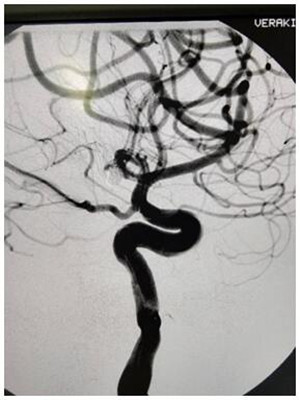

患者男性,39歲,以“頭痛2小時”急診入院,頭顱CT示:蛛網膜下腔出血,多考慮:動脈瘤破裂所致,需急診行腦動脈造影。護理人員在做好治療的同時,給予心里疏導,全程陪護病人,在進行3D旋轉時患者頭痛劇烈煩躁不安,造影圖像不清。為了獲取清晰的圖像準確定位,治療護士不顧輻射用自己的雙手固定住患者頭部,一旁還在患者耳邊殷殷囑咐:“這是最難受也是最重要時刻,需要配合堅持,很快就會結束!”在手術醫生嫻熟的技術下,造影順利結束。

經過大家3個小時的努力,在姚院長準確地判斷,經過團隊嫻熟手法和果斷地處置下,手術順利完成!麻醉復蘇后,患者清醒,頭痛緩解,無惡心,四肢肌力正常,生命體征平穩。